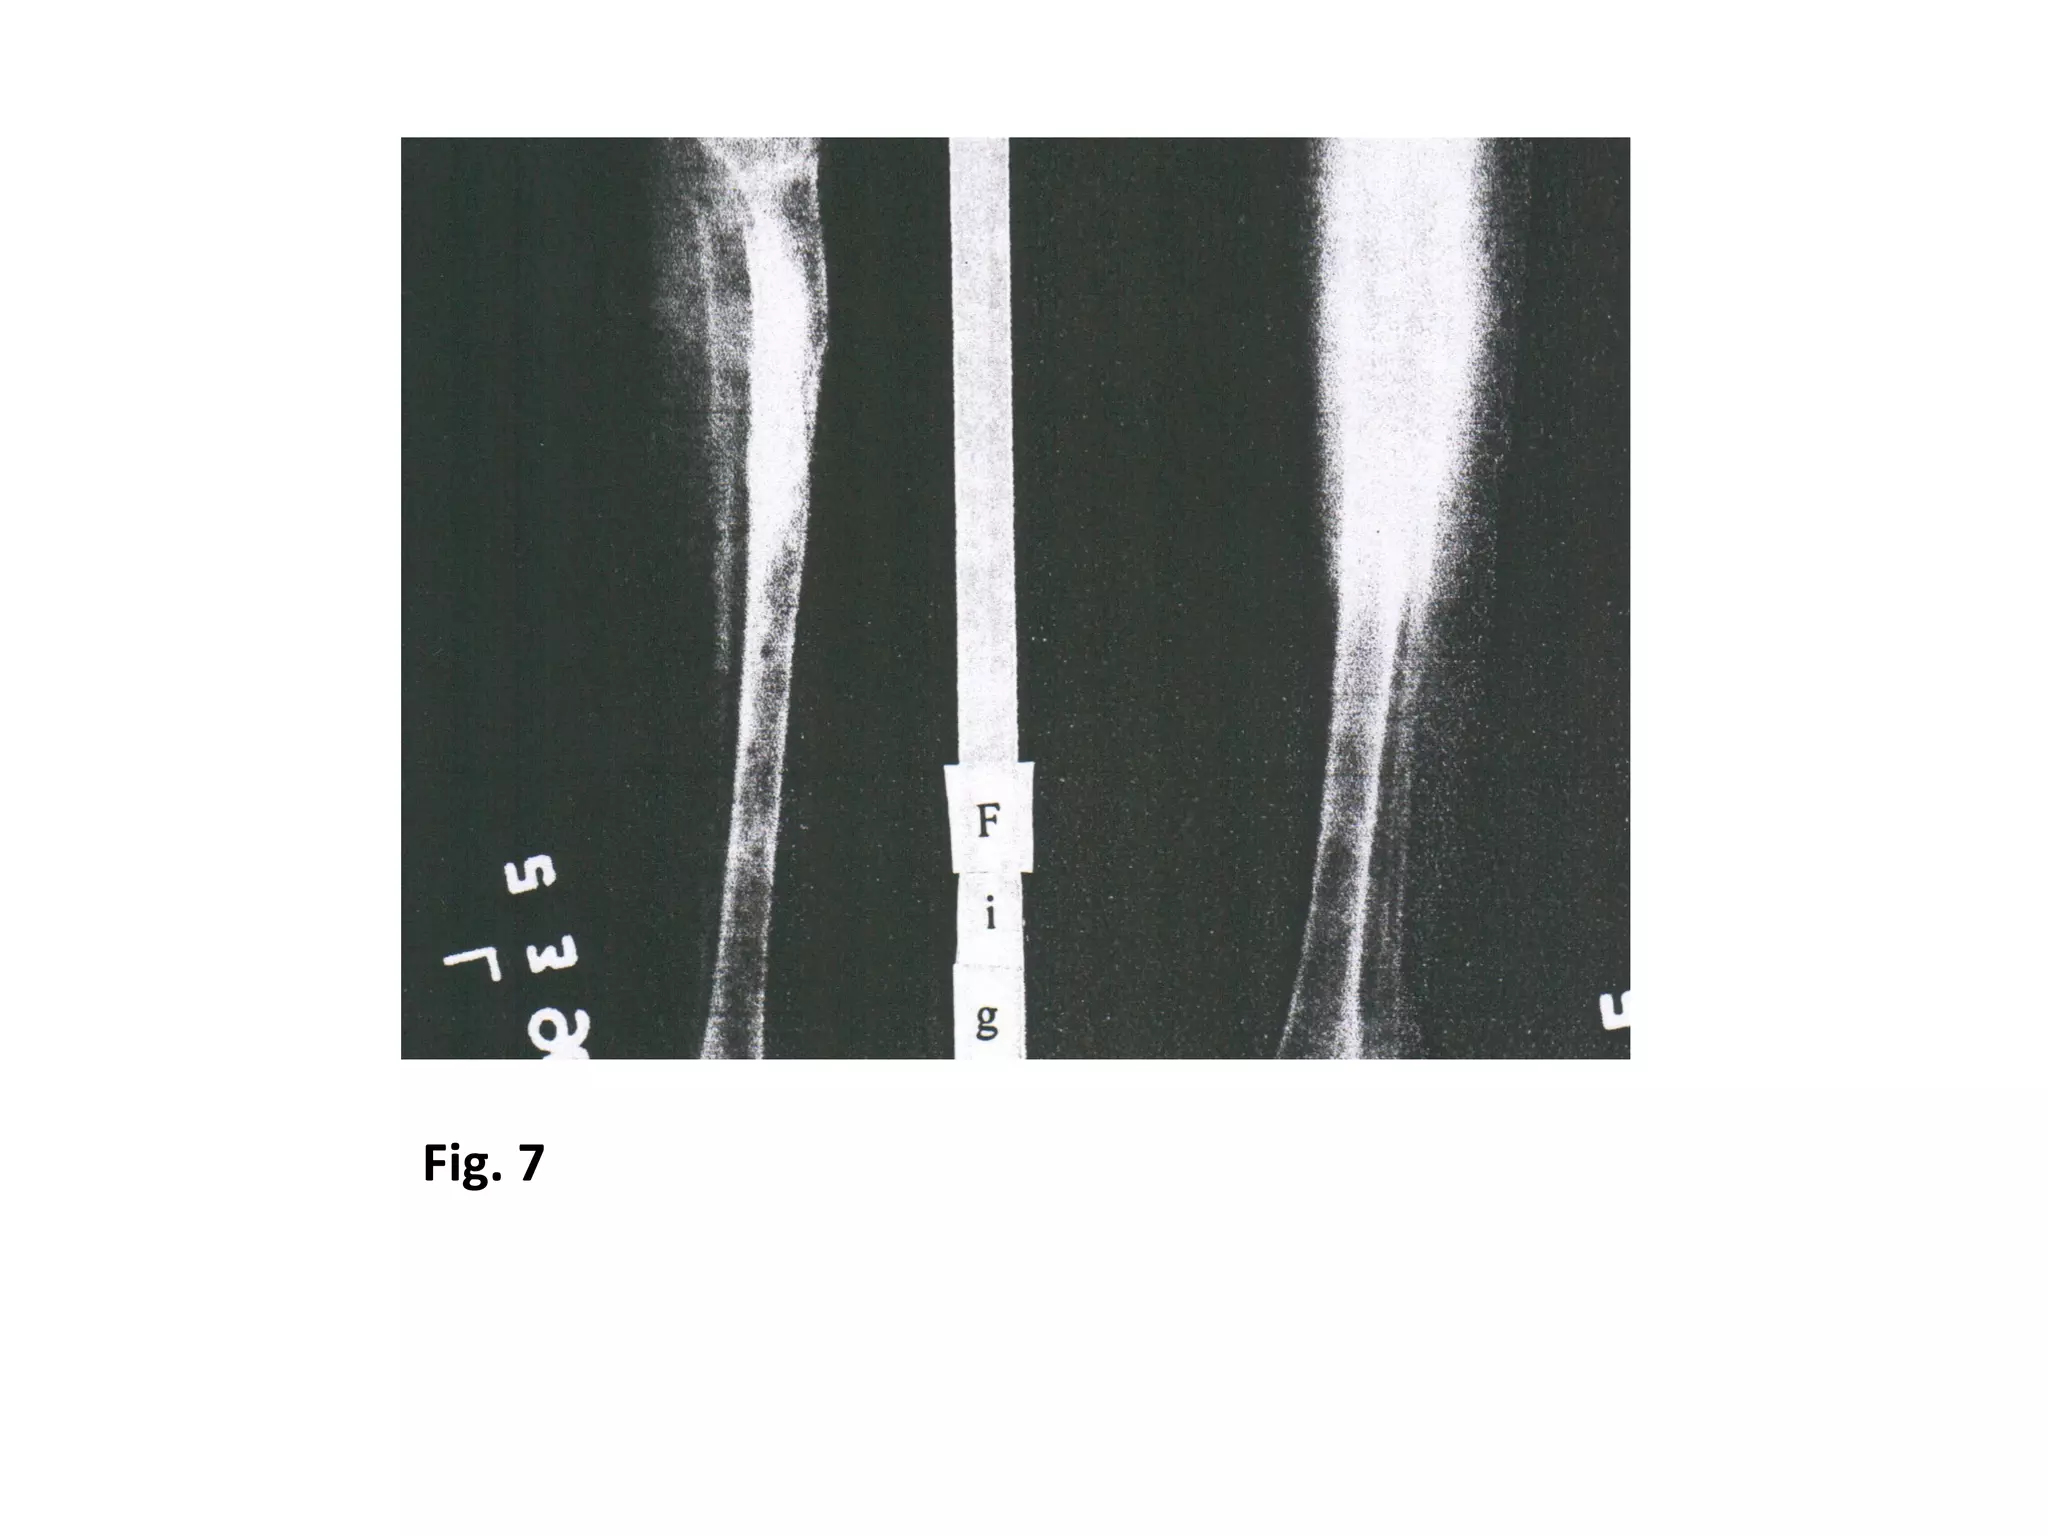

Fig. 7

Fig. 8

The bones are elongated, corticalized & the external fixator is removed.